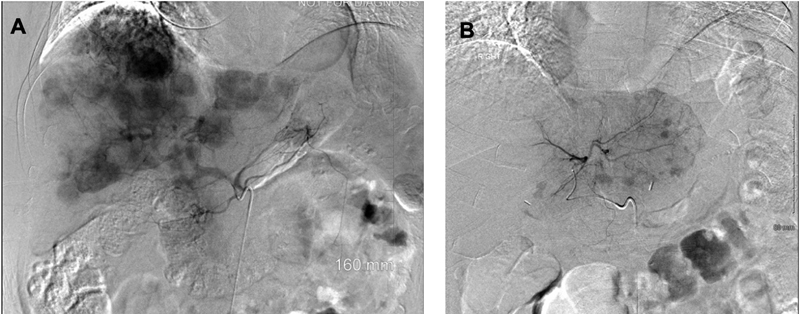

|?Fig. 1 (A) ? Celiac artery angiogram demonstrating multiple enhancing metastatic NET throughout the liver. (B) Left hepatic artery angiogram demonstrating enhancing metastatic NET in the left lobe of the liver (representative images; source: Department of Radiology, University of Kentucky). NET, neuroendocrine tumors.|

? She underwent right and left lobe liver bland embolization without complication. Also received palliative radiation therapy to the right hip. What systemic therapy is ideal now?